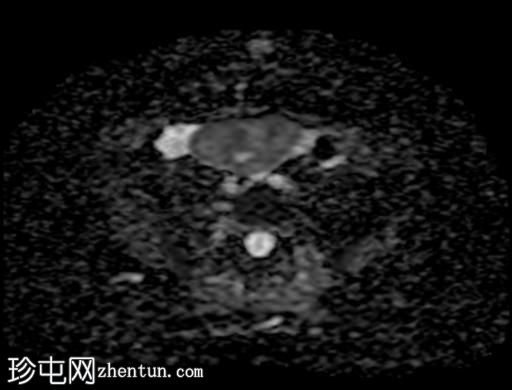

轴位

T2加权像

盆腔内可见多个边界清晰的肿块:

其中一个位于子宫上方,T2加权像呈中等信号,中心区域呈高信号,增强T1脂肪抑制像未见强化。右侧卵巢增大,增厚的血管蒂扭曲,未见强化,轴位和矢状位T2加权像均显示清晰。

另一个位于子宫后窝,T2加权像呈中等信号,增强扫描显示明显强化。

轻度腹腔积液